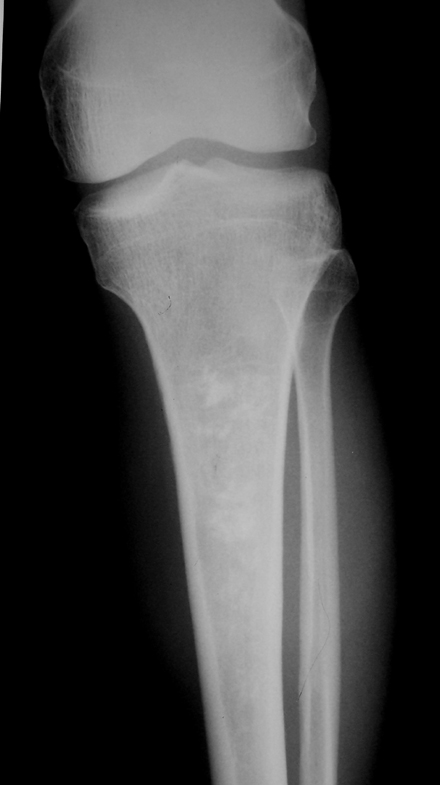

胫骨上段可见斑片状高密度影,密度不均,边界欠清,邻近骨质无破坏,无骨膜反应,周围软组织无肿胀。

多考虑骨梗死可能性大。

胫骨上段见有斑片状密度增高影,密度不均,周边骨质未见破坏,考虑骨梗塞.

胫骨中上段髓腔内可见斑片状钙化,边界较清楚,未见骨膜反应及软组织肿块影。

诊断:胫骨骨梗死。

右胫骨中段髓腔内见斑片状密度增高影,边缘清楚,密度不均,未见骨质破坏,无膨胀变形,周围无软组织肿块,考虑骨梗死。

胫骨上段可见斑片状高密度影,边界清楚,无骨质破坏,无软组织改变,应考虑骨梗死。

胫骨髓腔内多发形态不规则钙化/骨化影,呈蚓状分布,周围可见透亮带,骨质无破坏,无骨膜反应,无软组织块影,考虑骨梗死,鉴别诊断要和内生软骨瘤,骨斑点症等区分。